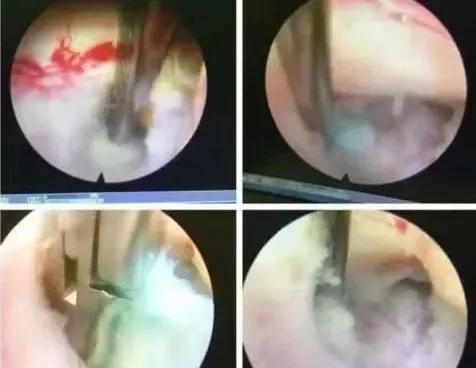

术中图示

经过脊柱关节外科中心会诊,诊断患者为神经根型颈椎病,根据患者的典型症状,医生建议行微创颈椎后路椎间孔切开术KEY-hole(钥匙孔技术)。在脊柱关节外科中心手术团队的共同努力下,手术过程顺利,术后患者恢复良好。